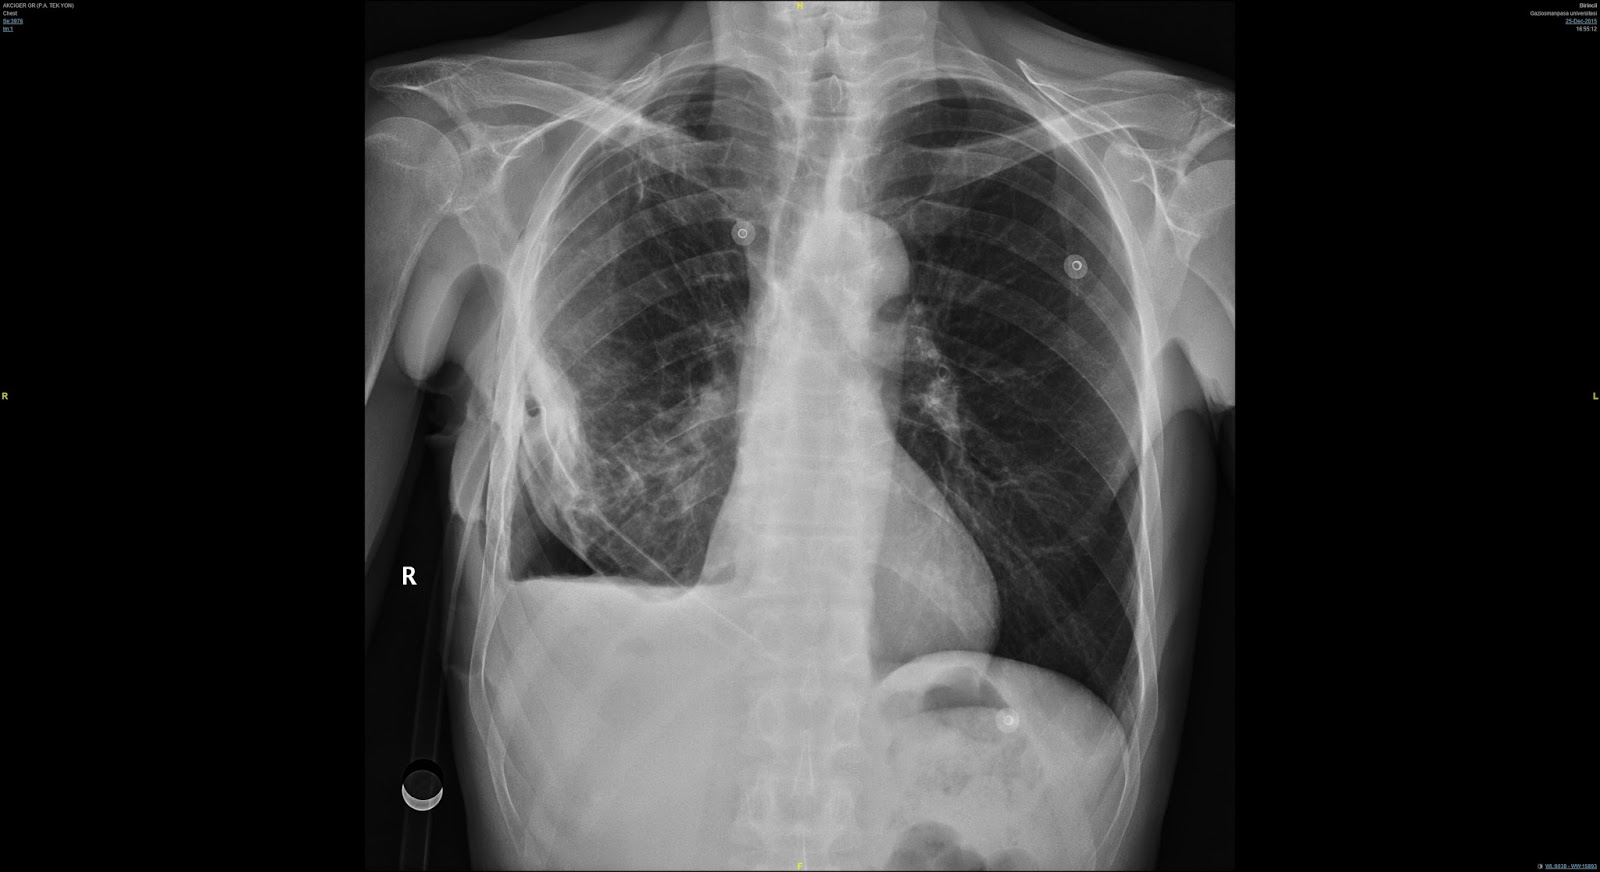

Рентген грудной клетки при гемотораксе: примеры и описание